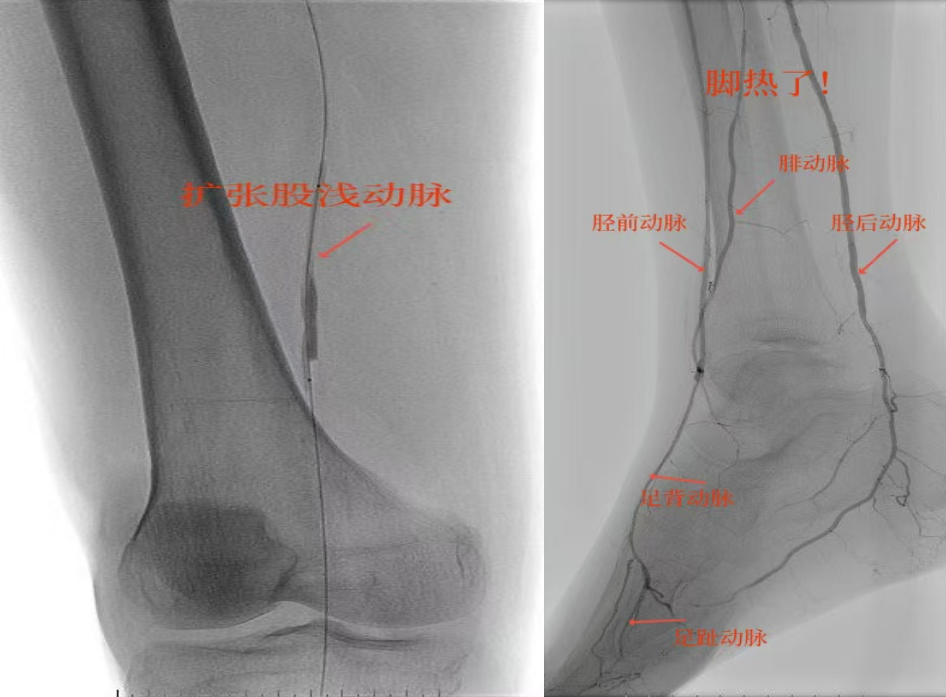

78歲男性患者,糖尿病合并高血壓、腦梗塞,右足持續(xù)疼痛伴冰涼發(fā)紺3個(gè)月。入院CTA顯示其右側(cè)股淺動(dòng)脈全程閉塞,膝下三支動(dòng)脈均閉塞。醫(yī)療團(tuán)隊(duì)在局部麻醉下,再次巧妙應(yīng)用“逆向開(kāi)通技術(shù)”,經(jīng)脛后動(dòng)脈——足底弓逆向開(kāi)通足背動(dòng)脈及脛前動(dòng)脈。術(shù)后患者右足皮溫即刻回升,疼痛消失。術(shù)后結(jié)合中藥外治(換藥、熏洗、去腐生肌膏外敷)加速創(chuàng)面愈合,患者已順利出院。

影像檢查:CTA顯示右側(cè)股淺動(dòng)脈全程閉塞,膝下三支動(dòng)脈(脛前、脛后、腓動(dòng)脈)完全閉塞。

兩例患者共同凸顯三大高難度治療挑戰(zhàn):1.患者高齡且基礎(chǔ)病復(fù)雜;2.血管全程多節(jié)段閉塞、鈣化程度嚴(yán)重;3.常規(guī)順向開(kāi)通路徑已被完全阻斷。團(tuán)隊(duì)果斷采用遠(yuǎn)端逆行穿刺技術(shù),在纖細(xì)的足踝部血管建立治療通道,實(shí)現(xiàn)“逆向破冰”。

“逆向開(kāi)通操作技術(shù)”就像在復(fù)雜的血管迷宮中反向找“出口”。介入血管外科楊彥林副主任形象地比喻道,“該操作技術(shù)突破了傳統(tǒng)順向開(kāi)通的技術(shù)局限,為瀕臨截肢的晚期糖足患者提供了寶貴的保肢新選擇。”目前該方案已成為我院治療復(fù)雜下肢動(dòng)脈病變的常規(guī)手段。